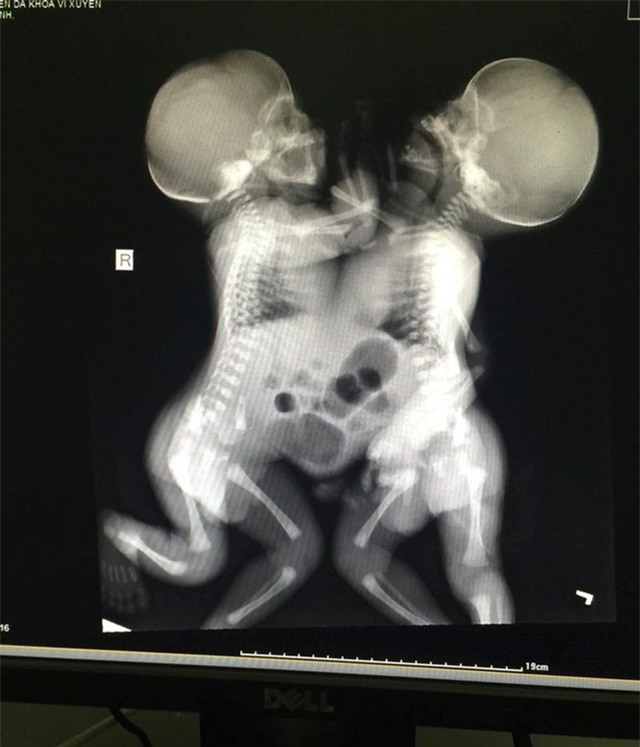

Lúc ấy các bác sĩ chỉ biết là thai đôi chứ không biết là hai thai dính nhau. Trong quá trình mổ sinh, bác sĩ phát hiện 2 bé trai dính liền với nhau từ ngực đến bụng, chung dây rốn, 2 thai có trọng lượng 4900gr.

Sau mổ 2 cháu đang được chăm sóc tại khoa Nhi - Bệnh viện Vị Xuyên. Sáng ngày 14.7, bệnh viện đã hội chẩn có cả ban lãnh đạo bệnh viện và qua thăm khám sơ bộ, các bộ phận tim phổi thận của hai cháu vẫn tách rời nhưng để chẩn đoán tốt hơn bệnh viện phải chuyển hai bé xuống Hà Nội.